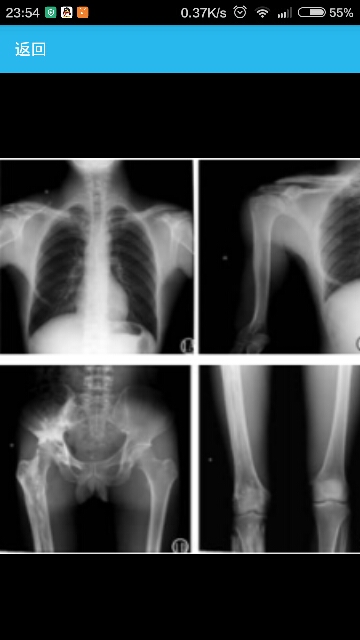

21岁男性,右下肢及右足间歇性疼痛,活动受限10余年,劳累后加重,辅助检查血钙、血磷、碱性磷酸酶、血沉、类风湿因子正常。 X线片示右锁骨、肩胛骨、肱骨、第六肋、第一掌骨、骶骨、髂骨、耻骨、股骨、胫腓骨及足诸骨均见骨质增生硬化,呈不规则斑片状、条状、团片状致密影,右肱骨、股骨骨皮质增生硬化以外侧明显,病变以向髓腔内发展为主,髓腔变窄或消失,骨小梁消失,似蜡油流过样,骨皮质外缘光滑;病变诸骨未见明确骨质破坏征象;各关节关节面尚光滑,关节间隙清晰;周围软组织未见异常密度影(图1A-1G)。右股骨、胫腓骨骨干增粗,胫腓骨有弯曲变形(图1D-1F);心肺、腰骶椎、头颅及左侧胸、肢体、骨盆诸骨未见异常。

诊断:蜡油样骨病。